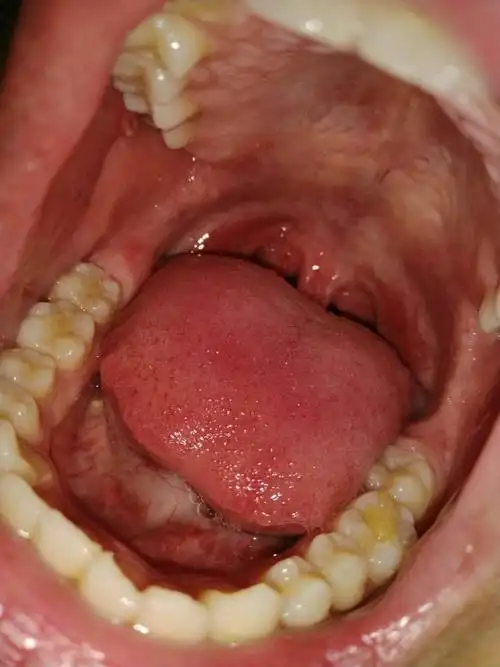

这是什么情况,口腔壁长泡能自愈吗

前几天吞咽有点疼痛,看到口腔内壁有个白点,不痛,就是有点膈应.

我得口腔怎么治疗,如图请请指教 现在症状是喉咙不舒服,肺呼吸有点疼